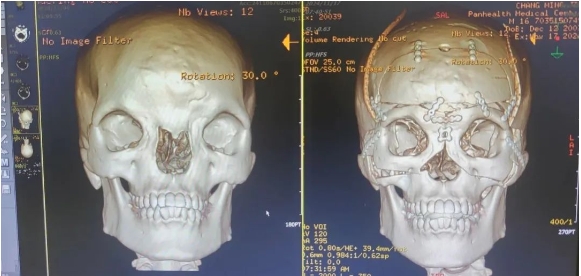

術(shù)前,整形外科劉斌團隊聯(lián)合醫(yī)院影像中心,為初晨完善顱頜面部CT三維重建,進行全面評估。為精準(zhǔn)的測量截骨量以防止術(shù)后復(fù)發(fā)和矯正不足,劉斌團隊選擇利用計算機輔助技術(shù)模擬多次切割,來設(shè)計精準(zhǔn)的截骨線,從而避免可能出現(xiàn)的遠期并發(fā)癥,并達到確切的美學(xué)效果。

手術(shù)非常順利,術(shù)后CT影像診斷報告顯示(如下圖),手術(shù)效果非常好,初晨兩眼骨性距離縮短至27mm,已在正常男性眼距范圍內(nèi)。